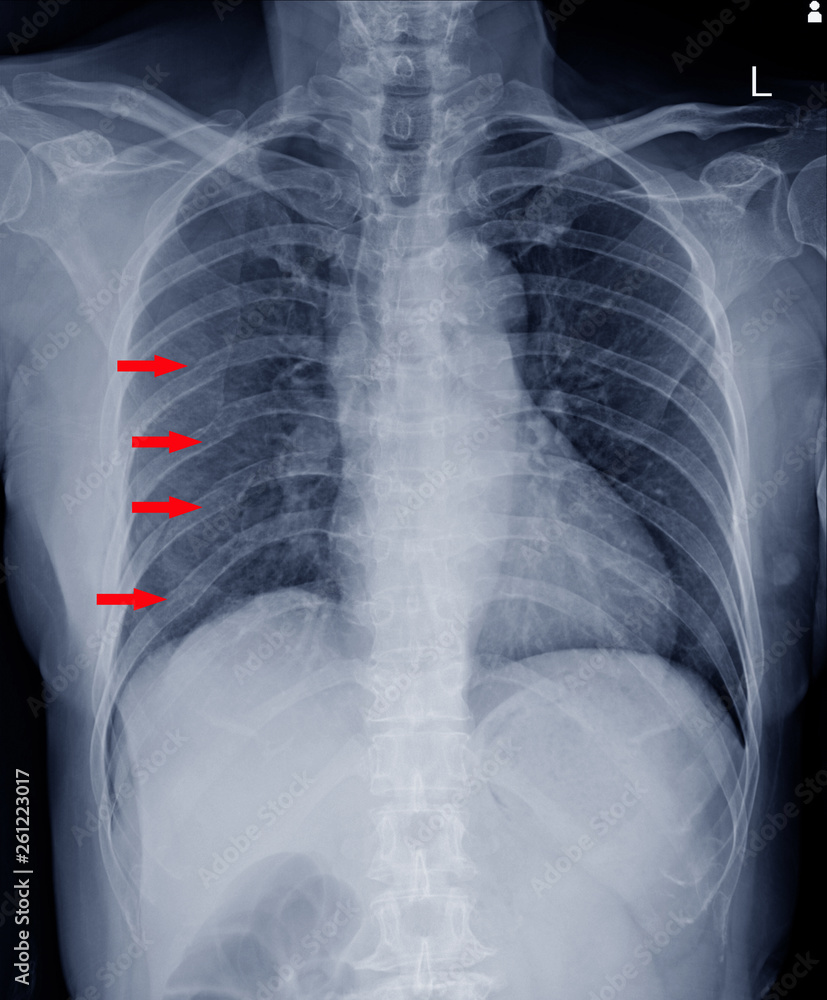

xray chest.finding Multiple fracture ribs on red arrows mark. Stock On Q Pump Rib Fractures Web rib fractures are common injuries that occur most often following blunt thoracic trauma but can also result from. Web multiple rib fractures are associated with a significantly increased morbidity and mortality compared to single rib fractures. Rib fractures are a significant health burden in terms of morbidity and mortality, especially in the elderly. Web when adjusting for number of. On Q Pump Rib Fractures.